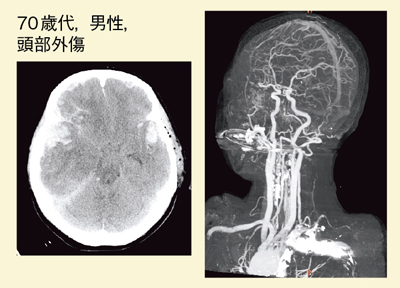

● 症例3:転移性腫瘍

左頭頂葉に皮下出血があり,CTAでは動脈瘤などの異常血管はないが,早期相,遅延相で血腫内に造影剤漏出が認められる80歳代,男性の症例である(図8)。造影CT(DE)の遅延相を処理すると(図9),ヨード画像では,血腫内に薄い濃染が認められ(図9b),何らかの腫瘤性病変が疑われる。

この症例は,入院後に右上下肢の麻痺の進行,失語症状の増悪が見られたため,CT再検査を行ったところ血腫の増大が認められ,緊急開頭血腫除去術が施行された。血腫内に腫瘤病変があり,metastatic adenocarcinoma(転移性腺癌)と診断された。血腫内の淡く染まるような病変を,DEイメージングのbrain hemorrhageで検出できる可能性が示唆された症例である。

![]() 図8 症例3:転移性腫瘍(頭部CT) |